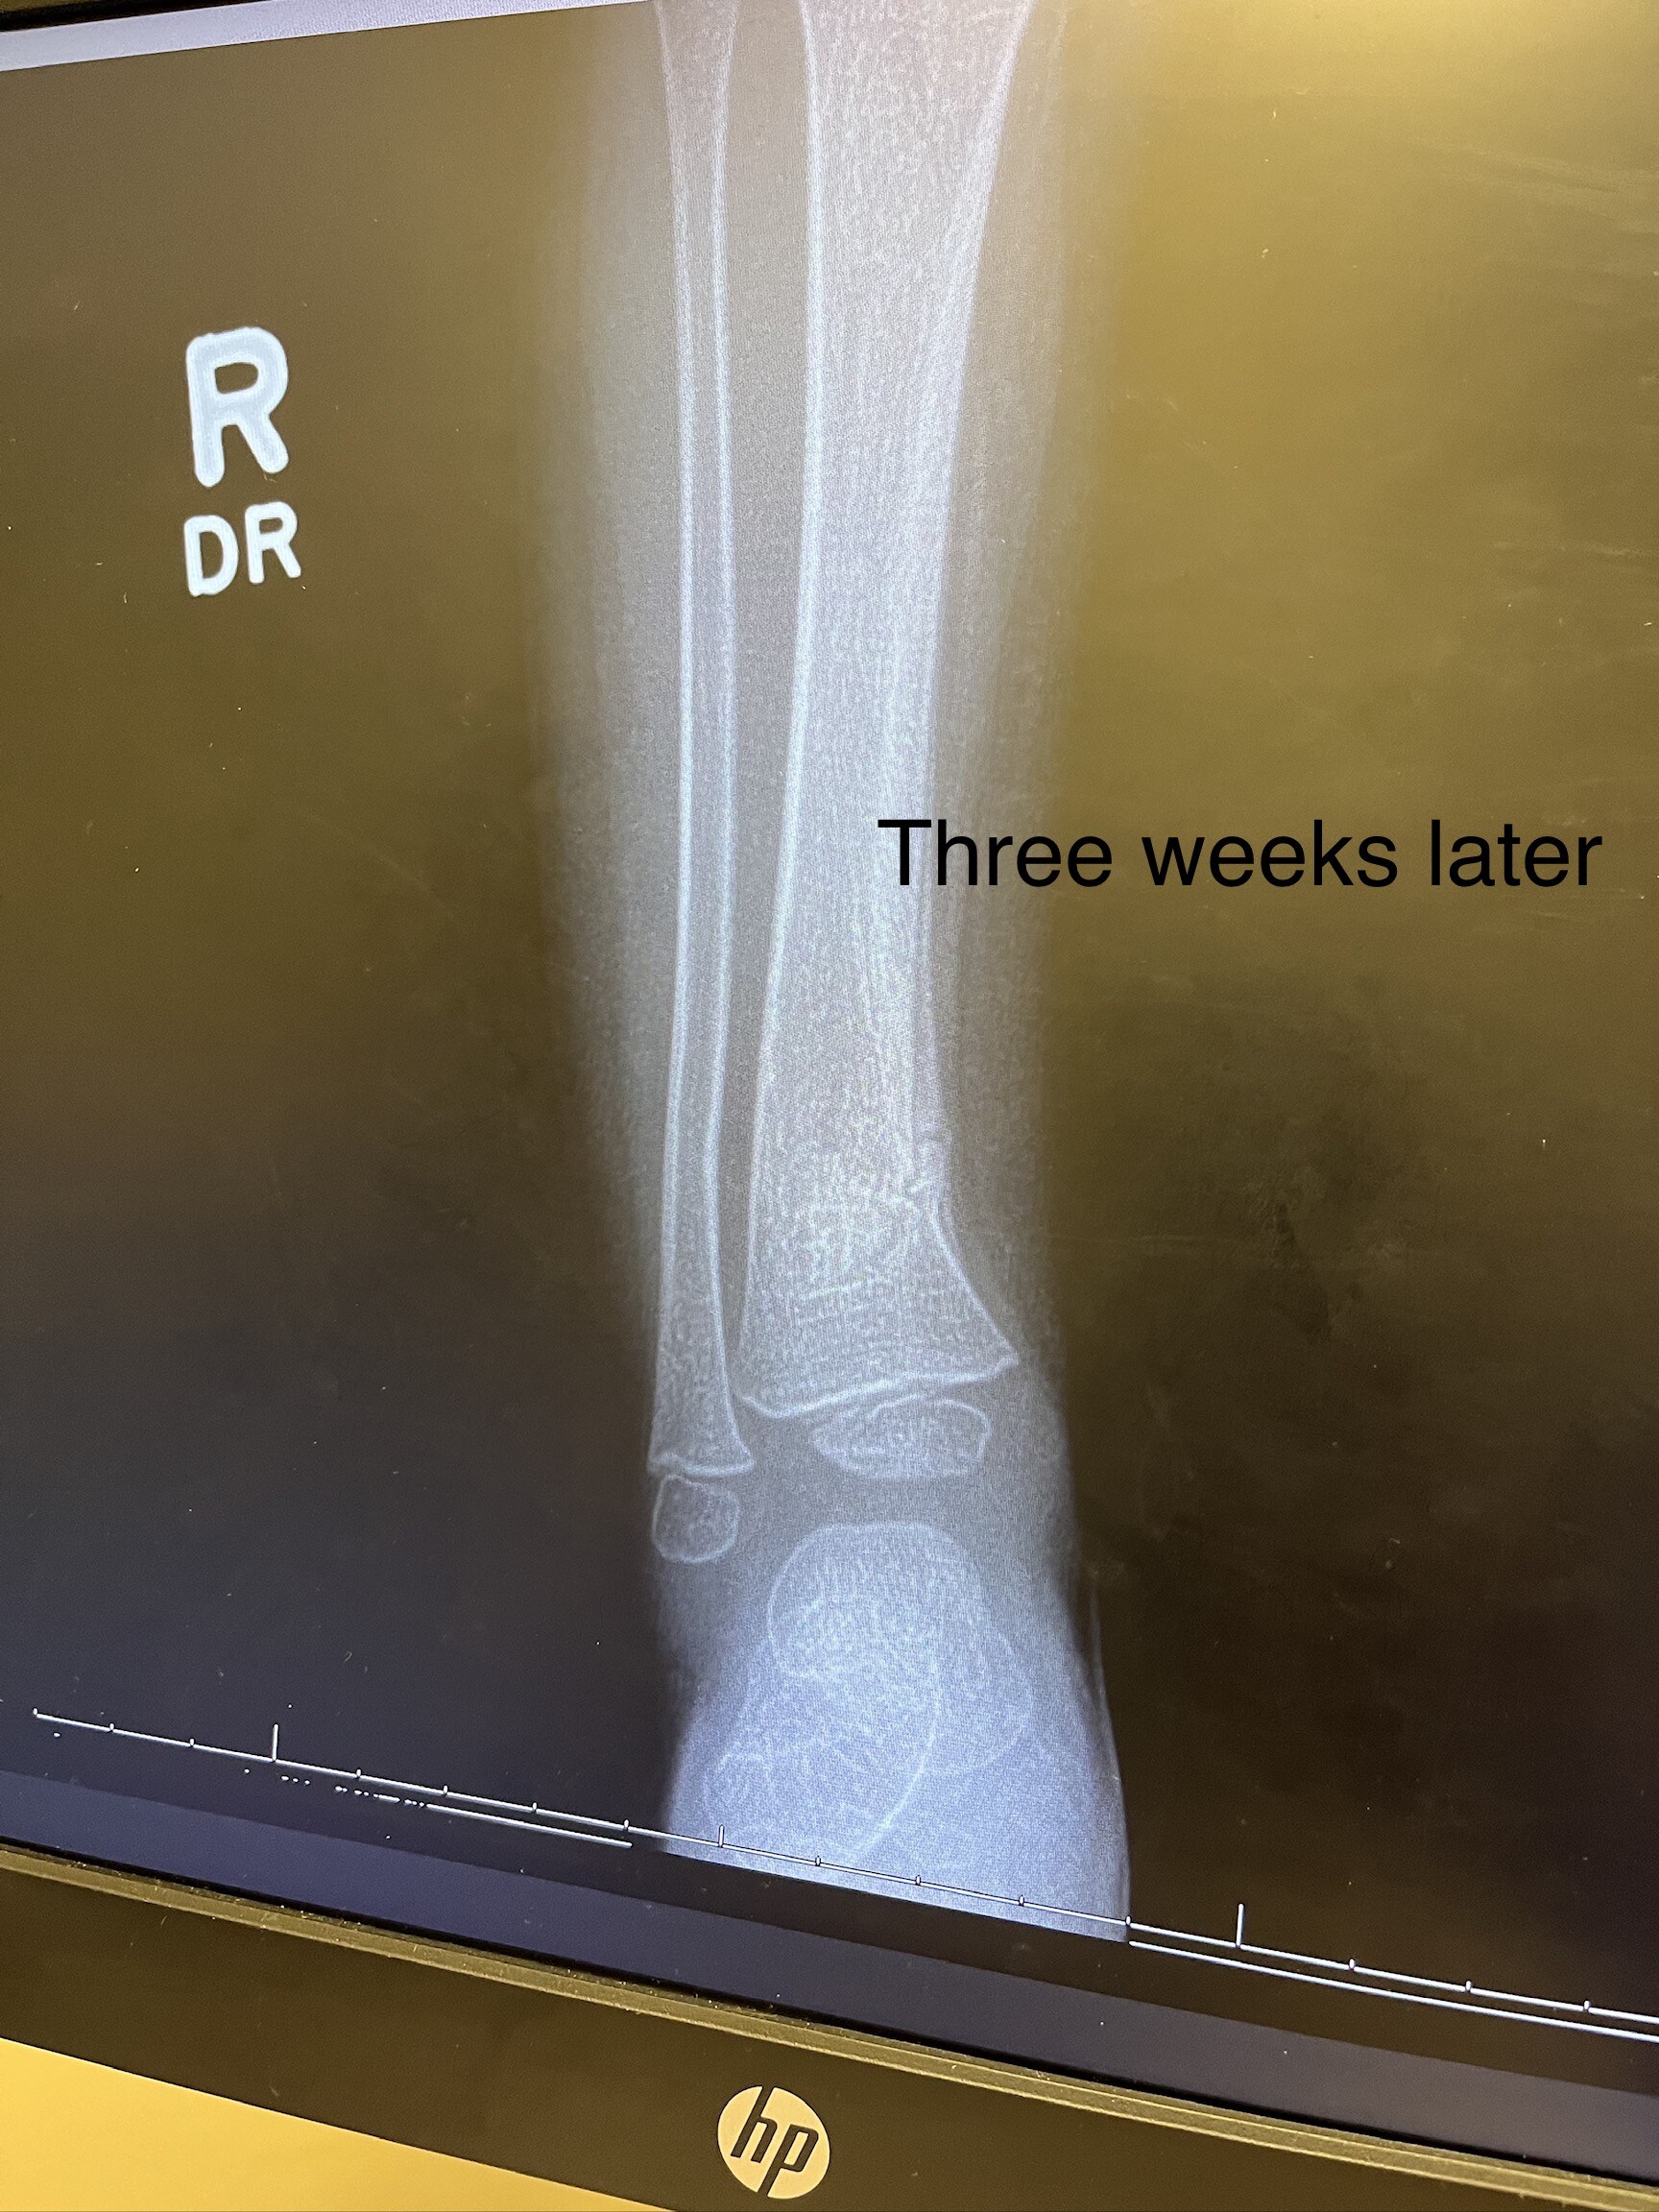

Last month my 2 year old daughter slid awkwardly down a playground rock wall and broke her leg. Specifically, she had a mild tib-fib fracture. That stands for tibia and fibula which are the two bones of the lower leg. That first week was terrible. We had a child with 2 year old opinions stuck with the mobility of a 7 month old. By the third week of having the cast, she was running and jumping in the cast. After just three weeks they removed the cast! Three weeks! When kids are that young their body heals extremely fast. I would not wish that experience on any kid or parent but… as a medical professional, I found it fascinating! Now I get to share a little about the bone healing process with you using her actual x-rays.

After the initial break your body mounts that inflammatory response. This is an important step for removal of any waste or foreign bacteria but also to bring nutrient rich blood to the area. After the inflammatory phase your body creates a callous around the bone. This callus is initially soft but as those osteoblasts work that callus hardens and the break is surrounded by more bone than it needs. That area is now strong but it is not the ideal shape for function and energy transfer and so your body begins to remodel and slowly shave down the bone back to the perfect shape. Incredible!